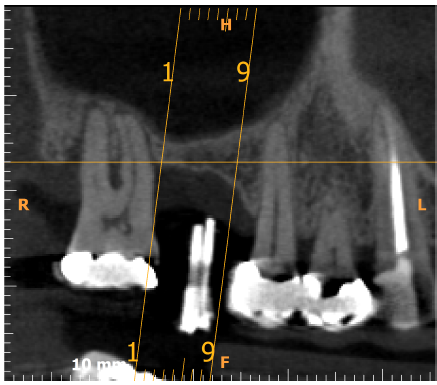

The bone used in a sinus lift may come from your own body (autogenous bone), from a cadaver (allogeneic bone) or from cow bone (xenograft). You will need X-rays taken before your sinus lift so the dentist can study the anatomy of your jaw and sinus. You also may need a special type of computed tomography (CBCT) scan. This scan will allow the dentist to accurately measure the height and width of your existing bone and to evaluate the health of your sinus.

The key to a successful and long-lasting dental implant is the quality and quantity of jaw bone to which the implant will be attached. If bone loss has occurred due to injury or periodontal disease, a sinus augmentation can raise the sinus floor and allow for new bone formation.

If enough bone between the upper jaw ridge and the bottom of the sinus is available to stabilize the implant well, sinus augmentations and implant placement can sometimes be performed as a single procedure. If not enough bone is available, the sinus augmentation will have to be performed first, then the graft will have to mature for several months, depending upon the type of graft material used. Once the graft has matured, the implants can be placed.